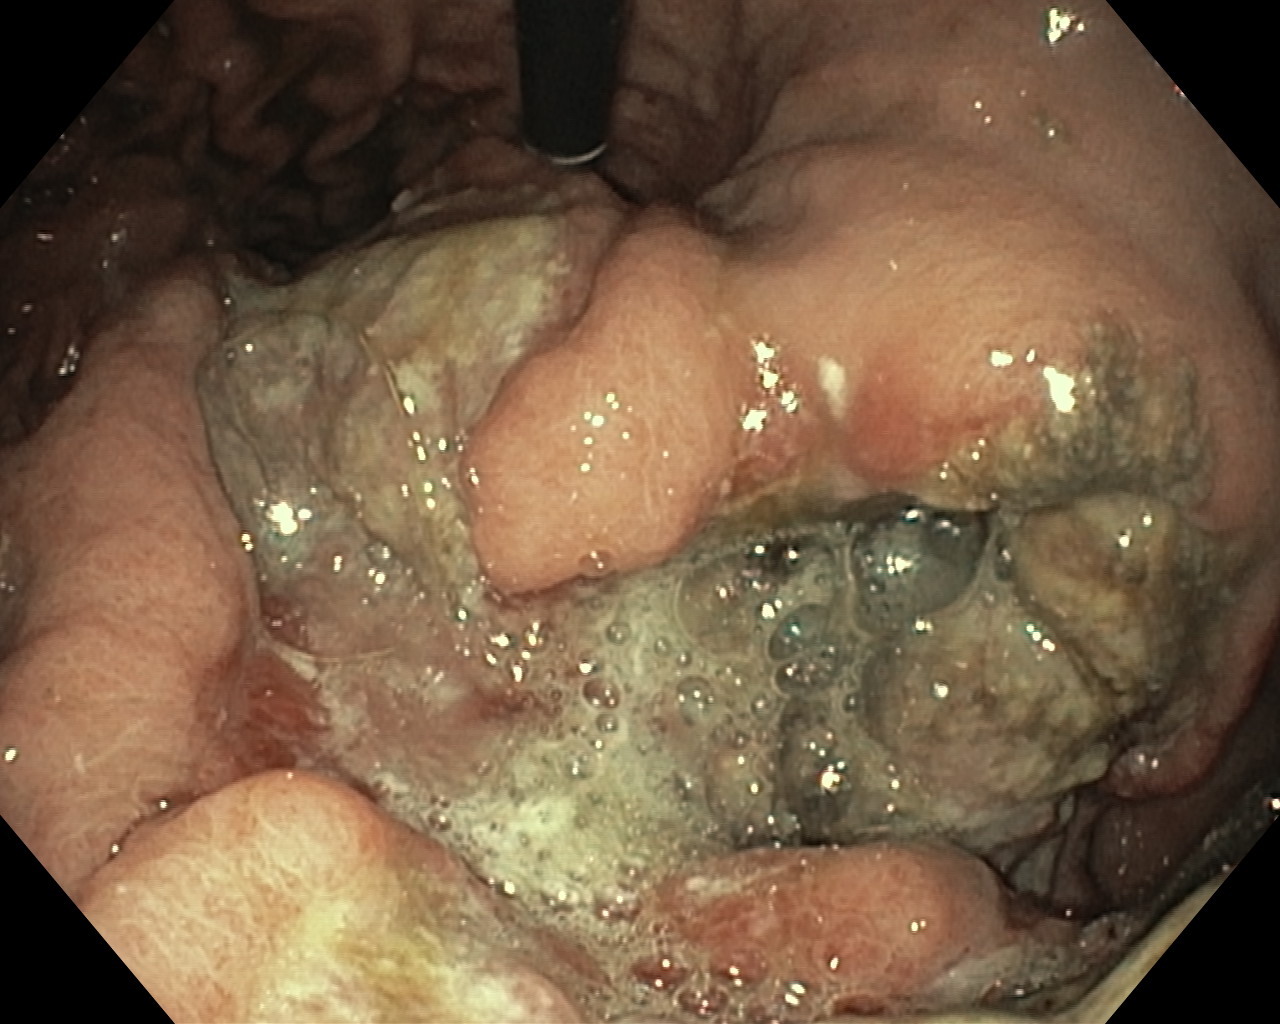

Nowotwory przewodu pokarmowego